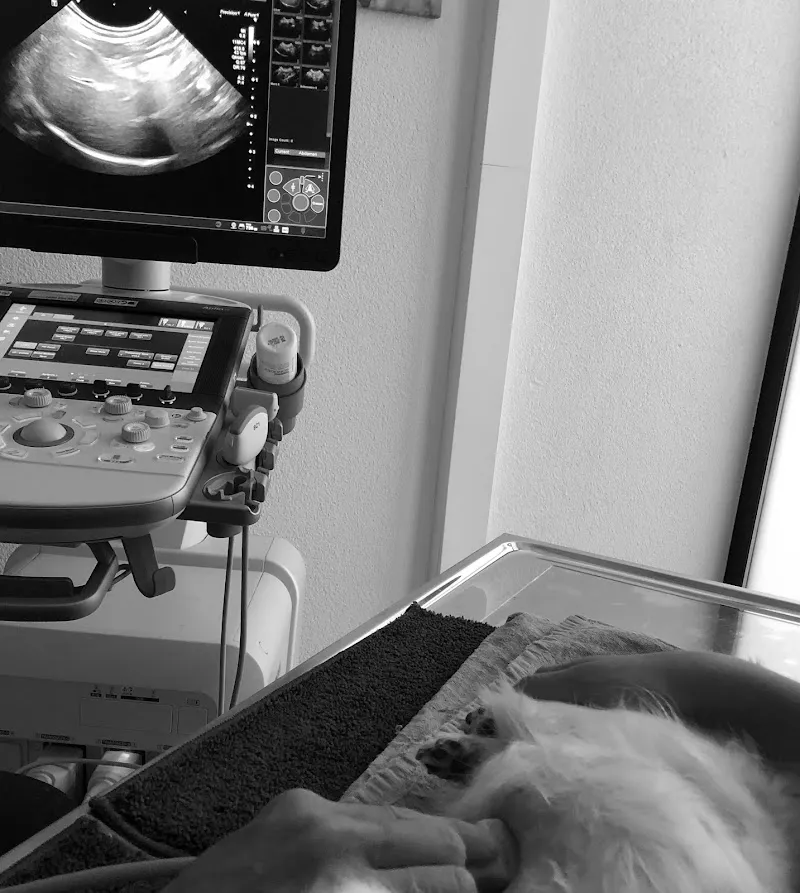

📍 Wechselächerstrasse 39, 8103 UnterengstringenDURCHBLICK-vet ist ein Tierdienst in Unterengstringen, Kanton Zürich. Schreiben Sie mir: info@durchblick-vet.ch für Rückfragen können Sie mich gerne anrufen: Tiere sind meine große Leidenschaft, und ihr Wohlbefinden liegt mir am Herzen. Ich habe mein Veterinärstudium in Bern abgeschlossen, wobei ich mich in meiner Dissertation mit chronischen Enteropathien bei Hunden, wie IBD und futtermittelbedten Enteropathien, beschäftigt habe. Anschließend absolvierte ich rotierendes Internship an der VetMedUni in Wien, wo ich die Faszination der Radiologiedeckte. Nach meiner Rückkehr in die Schweiz sammelte ich wertvolle klinische Erfahrungen verschiedenen Tierkliniken, bevor ich meine Residency in der bildgebenden Diagnostik an der Vetsuisse Fakultät Zürich begann. Seit 2018 bin ich Facharzt DECVDI (Diplomate of the European College of Veterinary Diagnostic Imaging) und unterstüt Tierärzte in der Bildgebenden Diagnostik. Dienstleistungen Support kontaktieren Wählen Sie ein Problem aus Wie kann ich helfen? Nadia Pfammatter, Dr. med. vet. DiplECVDI EVBS® Wechselächerstrasse 39 CH - 8103 Zürich © 2021 durchblick - vet Bewertet mit 5.0 von 5 Sternen (5 Bewertungen).